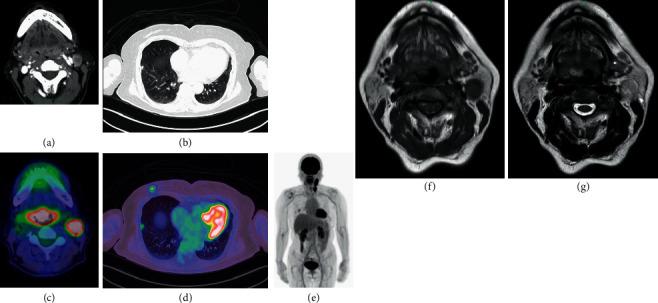

We report a case of amelanotic malignant melanoma (AMM) in a 66-year-old female. AMM of the lingual base was diagnosed based on a biopsy of late metastasis to the bone marrow of the L4 lumbar vertebra. The patient was initially treated with chemoradiotherapy after being misdiagnosed with poorly differentiated human papillomavirus- (HPV-) related squamous cell carcinoma of the oropharyngeal anterior wall. p16 immunostaining is used to diagnose HPV-related oropharyngeal cancer. However, while p16 expression is used as a surrogate marker of HPV infection, it is important to be aware that p16 protein overexpression can also be caused by other factors. Malignant melanoma is known to express the p16 protein. Morphologically differentiating between AMM and poorly differentiated squamous cell carcinoma based on hematoxylin-eosin staining is difficult. Therefore, in cases that are pathologically diagnosed as p16-positive poorly differentiated oropharyngeal squamous cell carcinoma, it is important to rule out AMM.

我们报告一例66岁女性的无色素性恶性黑色素瘤(AMM)。舌根部AMM是根据L4腰椎骨髓晚期转移的活检确诊的。该患者最初被误诊为口咽前壁低分化人乳头瘤病毒(HPV)相关鳞状细胞癌,之后接受了放化疗。p16免疫染色用于诊断HPV相关的口咽癌。然而,虽然p16表达被用作HPV感染的替代标志物,但必须注意p16蛋白过表达也可能由其他因素引起。已知恶性黑色素瘤会表达p16蛋白。基于苏木精-伊红染色在形态学上区分AMM和低分化鳞状细胞癌很困难。因此,在病理诊断为p16阳性的低分化口咽鳞状细胞癌的病例中,排除AMM很重要。